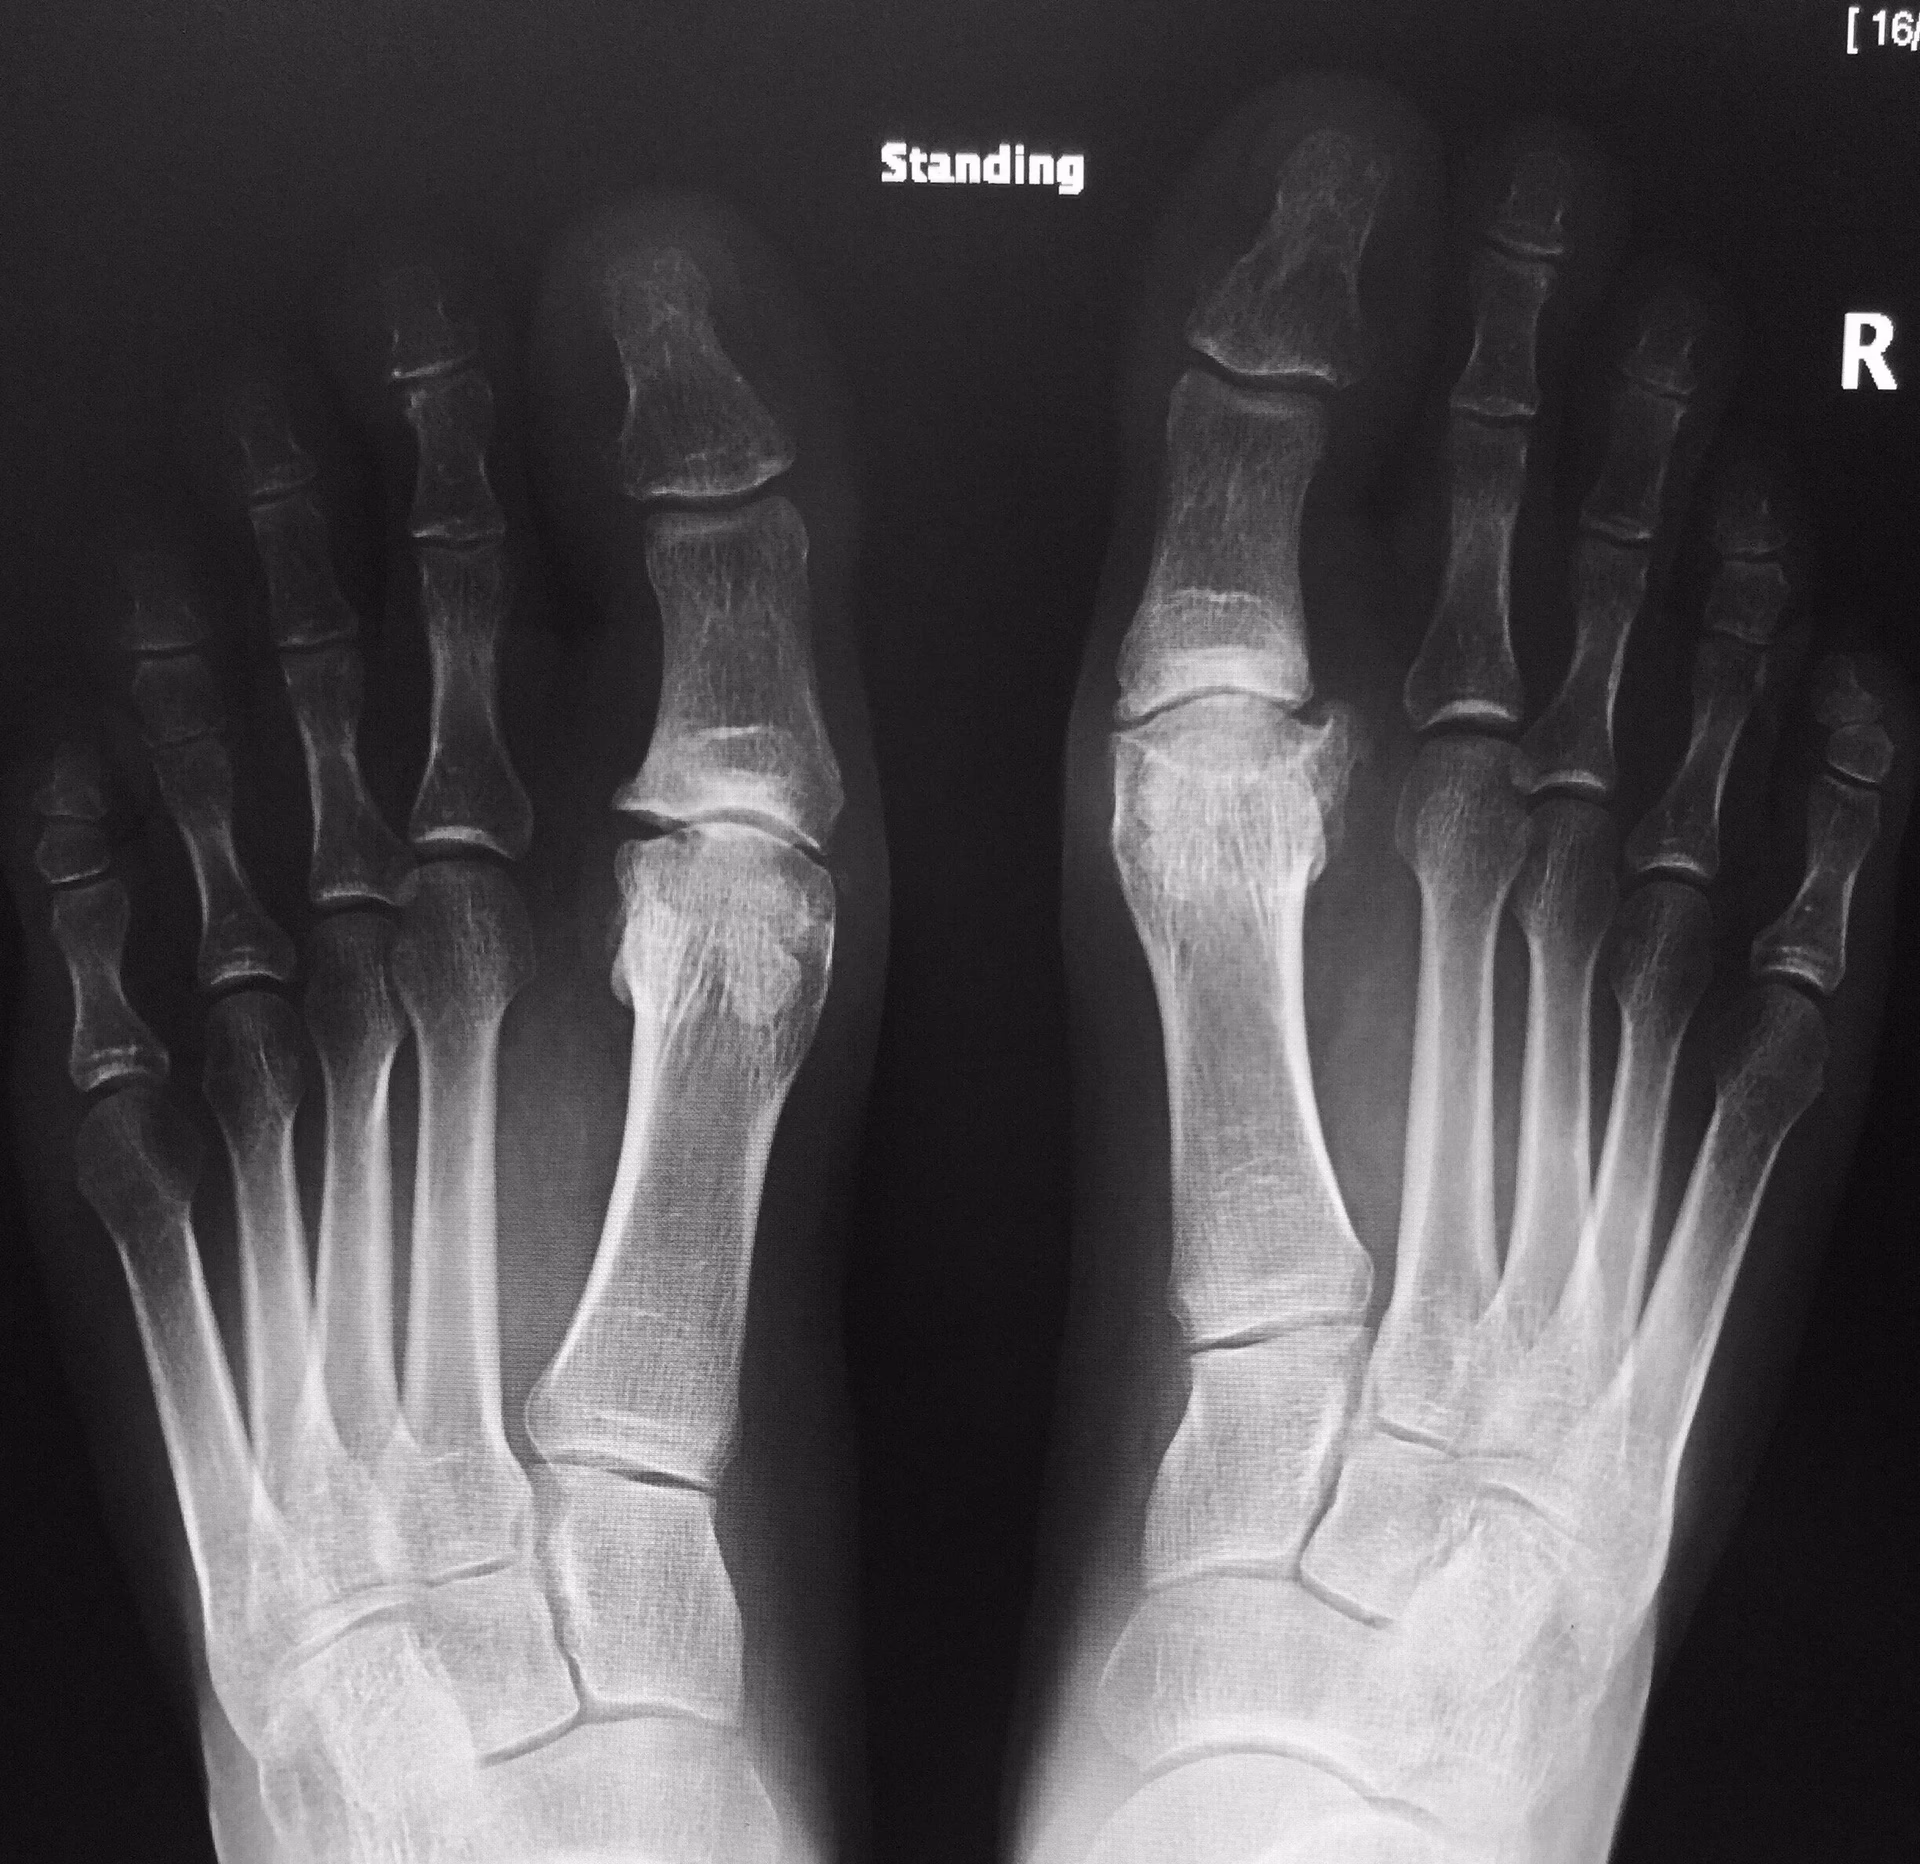

Udfordringerne ved Traditionel Diagnostik: Vægtbærende Røntgen

I årtier har vægtbærende almindelige røntgenbilleder været den primære metode til at diagnosticere knogle- og ledproblemer i foden. 'Vægtbærende' betyder, at billederne tages, mens patienten står op, så lægen kan se, hvordan knoglerne og leddene opfører sig under kroppens vægt. Dette er især vigtigt i foden, da mange problemer kun bliver tydelige under belastning.

På trods af dens udbredte anvendelse har vægtbærende røntgen betydelige begrænsninger, når det kommer til mellemfodsartrose:

- Overlejring af knogler: Mellemfoden er en tredimensionel struktur med mange små knogler, der ligger tæt på hinanden. På et todimensionelt røntgenbillede overlapper disse knogler hinanden, hvilket gør det ekstremt svært at få et klart billede af de enkelte ledspalter. Det kan være næsten umuligt at vurdere, om der er en indsnævring af ledspalten, hvilket er et kardinaltegn på artrose.

Baseret på den kliniske mistanke vil det første skridt i billeddiagnostikken næsten altid være et vægtbærende røntgenbillede. Det er hurtigt, billigt og let tilgængeligt. I mange tilfælde, især hvis artrosen er fremskreden, kan røntgenbilledet være tilstrækkeligt til at bekræfte diagnosen.

Det er vigtigt at huske, at billeddiagnostik altid skal ses i sammenhæng med patientens kliniske billede. En person kan have tegn på artrose på en scanning uden at have symptomer, og omvendt. Den endelige diagnose er en samlet vurdering af patientens historie, den fysiske undersøgelse og resultaterne fra billeddiagnostikken.